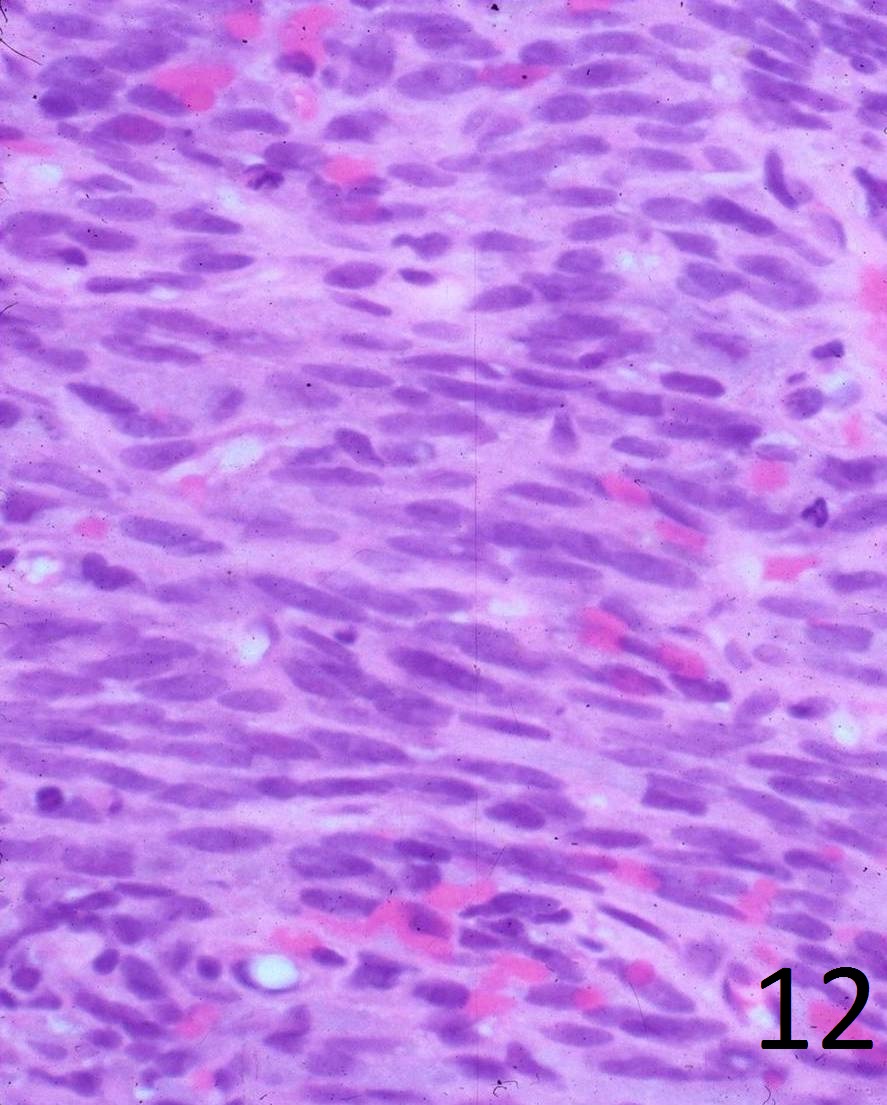

Histopathologic section of showing fascicles of Spindle Cell Fibrosarcoma Spindle cell tumor and spindle cell sarcoma are descriptive names used when tumor cells look long and narrow under the microscope. Spindle cell sarcoma is a rare form of bone cancer or soft tissue cancer. Spindle cell sarcoma is an extremely rare bone cancer. What is spindle cell sarcoma? A spindle cell sarcoma is a soft tissue tumor that originates. Spindle Cell Fibrosarcoma.

Bland spindle cells with a herringbone pattern, Haematoxylin and Eosin Spindle Cell Fibrosarcoma What is spindle cell sarcoma? Spindle cell sarcoma is an extremely rare bone cancer. Spindle cell sarcoma is a rare form of bone cancer or soft tissue cancer. Spindle cell tumor and spindle cell sarcoma are descriptive names used when tumor cells look long and narrow under the microscope. A spindle cell sarcoma is a soft tissue tumor that originates. Spindle Cell Fibrosarcoma.

H&E stain showing spindle cell neoplasm consistent with low grade Spindle Cell Fibrosarcoma A spindle cell sarcoma is a soft tissue tumor that originates in a bone. Spindle cell sarcoma is a rare form of bone cancer or soft tissue cancer. Spindle cell sarcoma is an extremely rare bone cancer. Spindle cell tumor and spindle cell sarcoma are descriptive names used when tumor cells look long and narrow under the microscope. What is. Spindle Cell Fibrosarcoma.